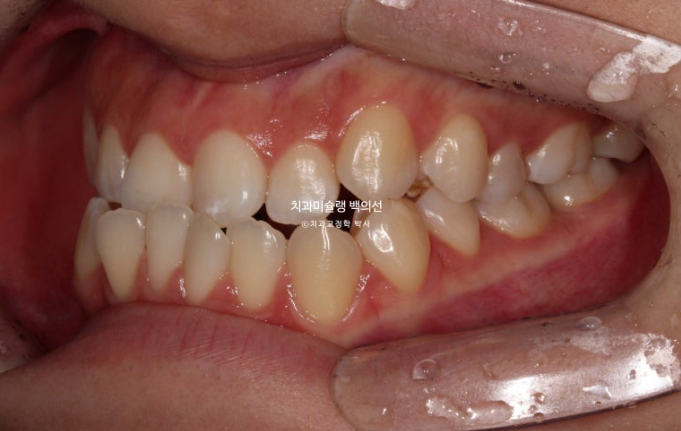

23.11~25.10

앞니가 거꾸로 물리는 반대교합이 해결되었습니다.